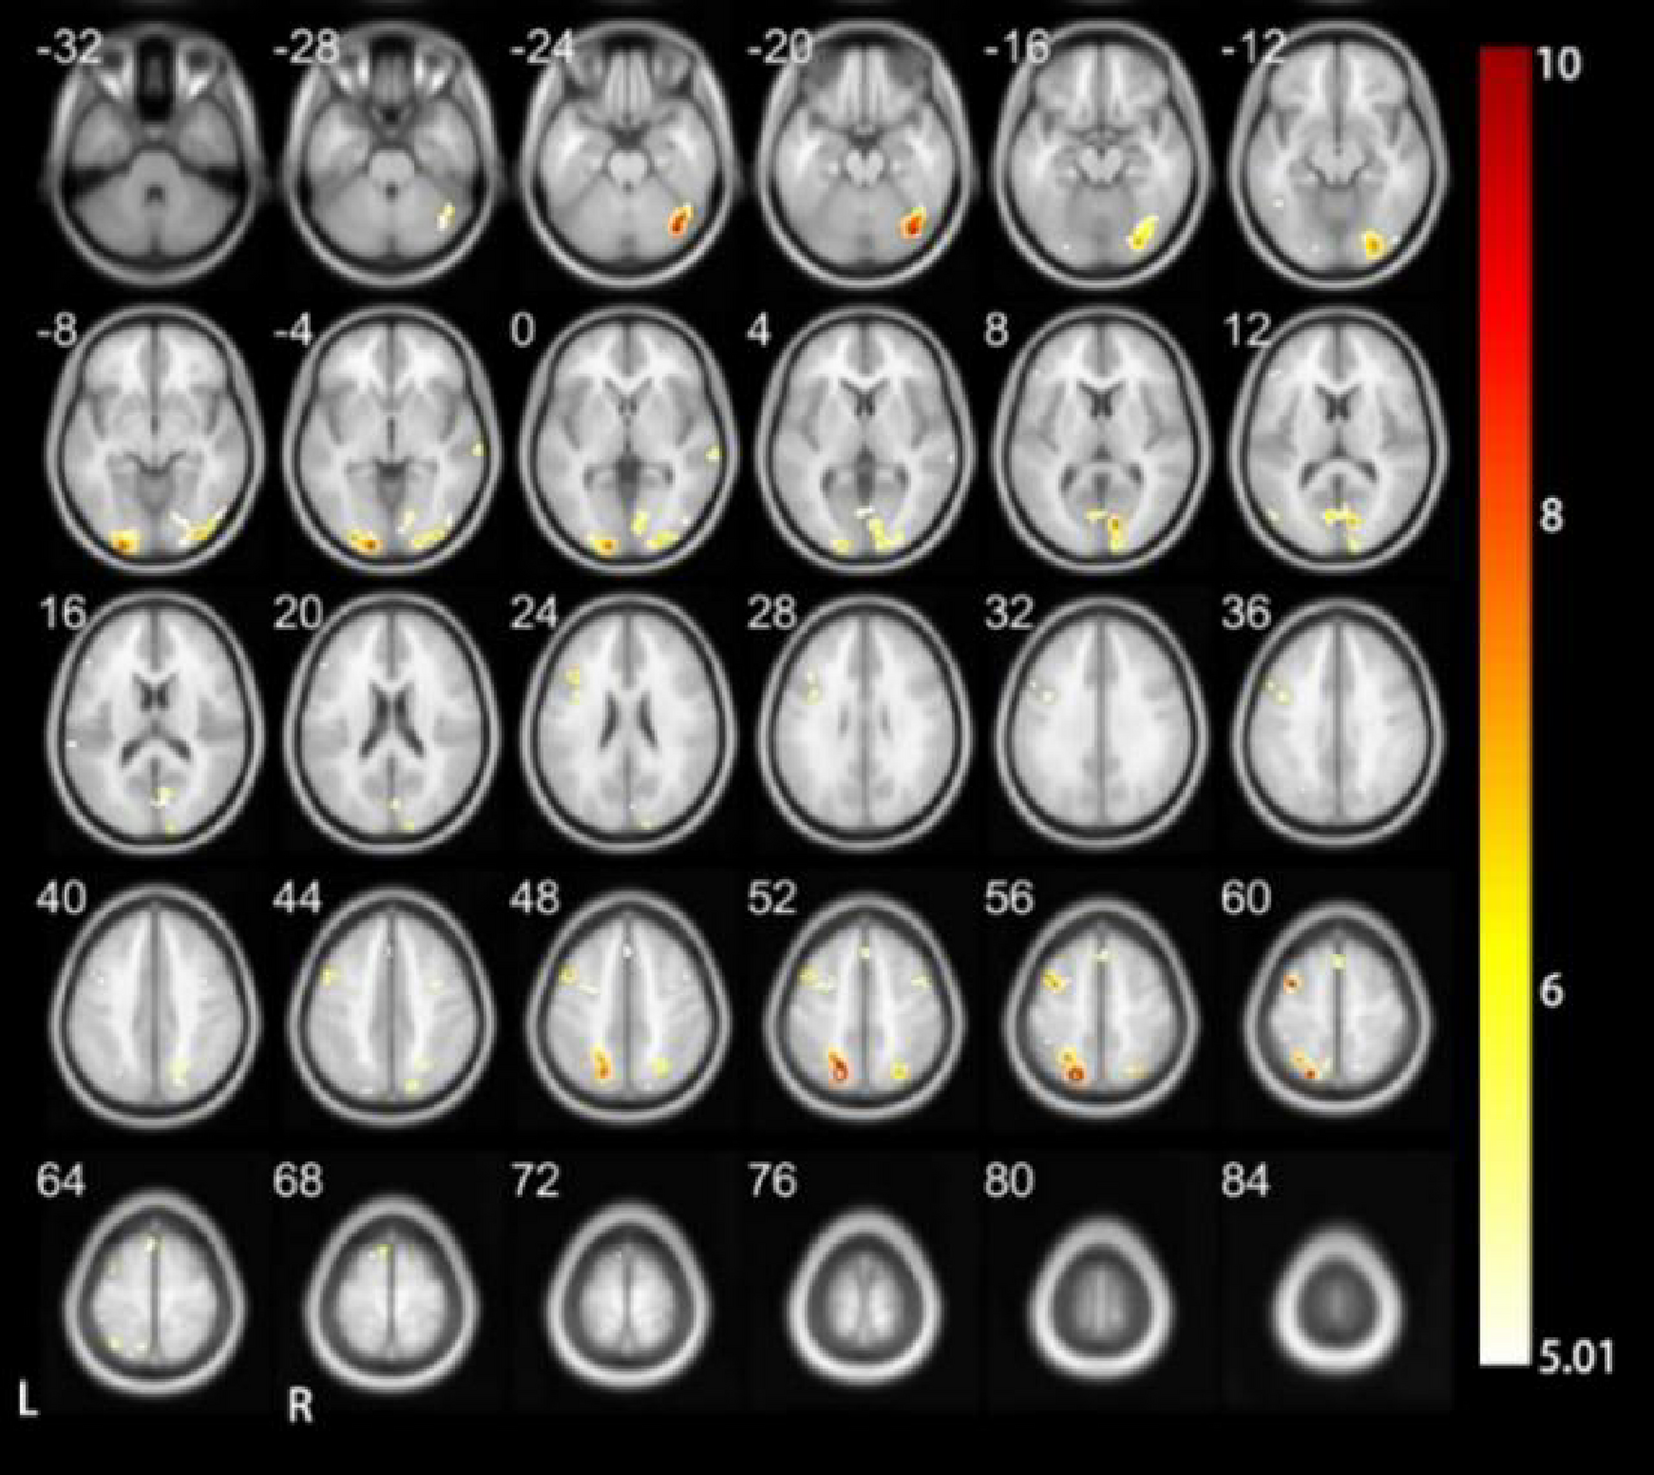

Fig. 5

Results of HC when performing the tone 2 task.